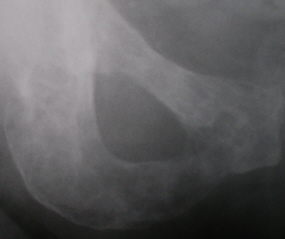

Иллюстрации 12, 13, 14. Остеопоротическая трансформация костной ткани грудных позвонков с формированием патологического гиперкифоза, в результате клиновидной деформации тел позвонков и их уплощения (патологические переломы). Множественные очаги деструкции костной ткани округлой формы, без четких контуров.